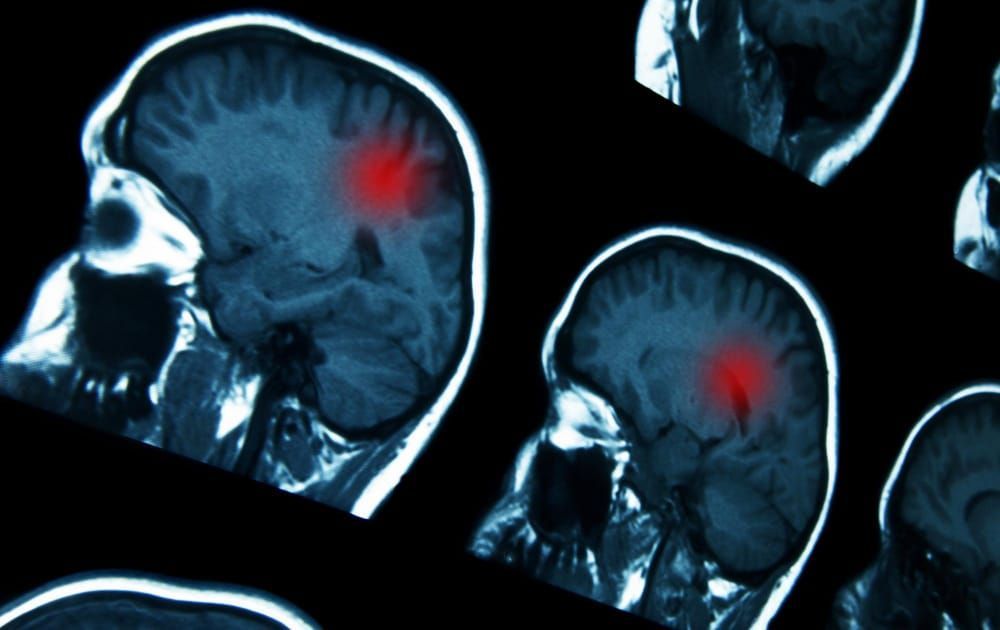

DiagnĂłstico

El diagnĂłstico de presunciĂłn es radiolĂłgico (RM cerebral o TAC) y el de confirmaciĂłn es histolĂłgico (analizando una muestra del tumor extraĂda por biopsia o tras la resecciĂłn quirĂşrgica del mismo)